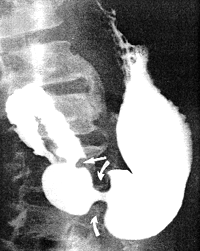

![]() |

| Fig. 13.2. Four monophasic duodenal pressure waves. Each was associated with a radiologically visible contraction. During each wave mucosal folds changed in direction to become longitudinal. Base line indicates intraluminal pressure in absence of motor activity. Ten-second marker on zero line |